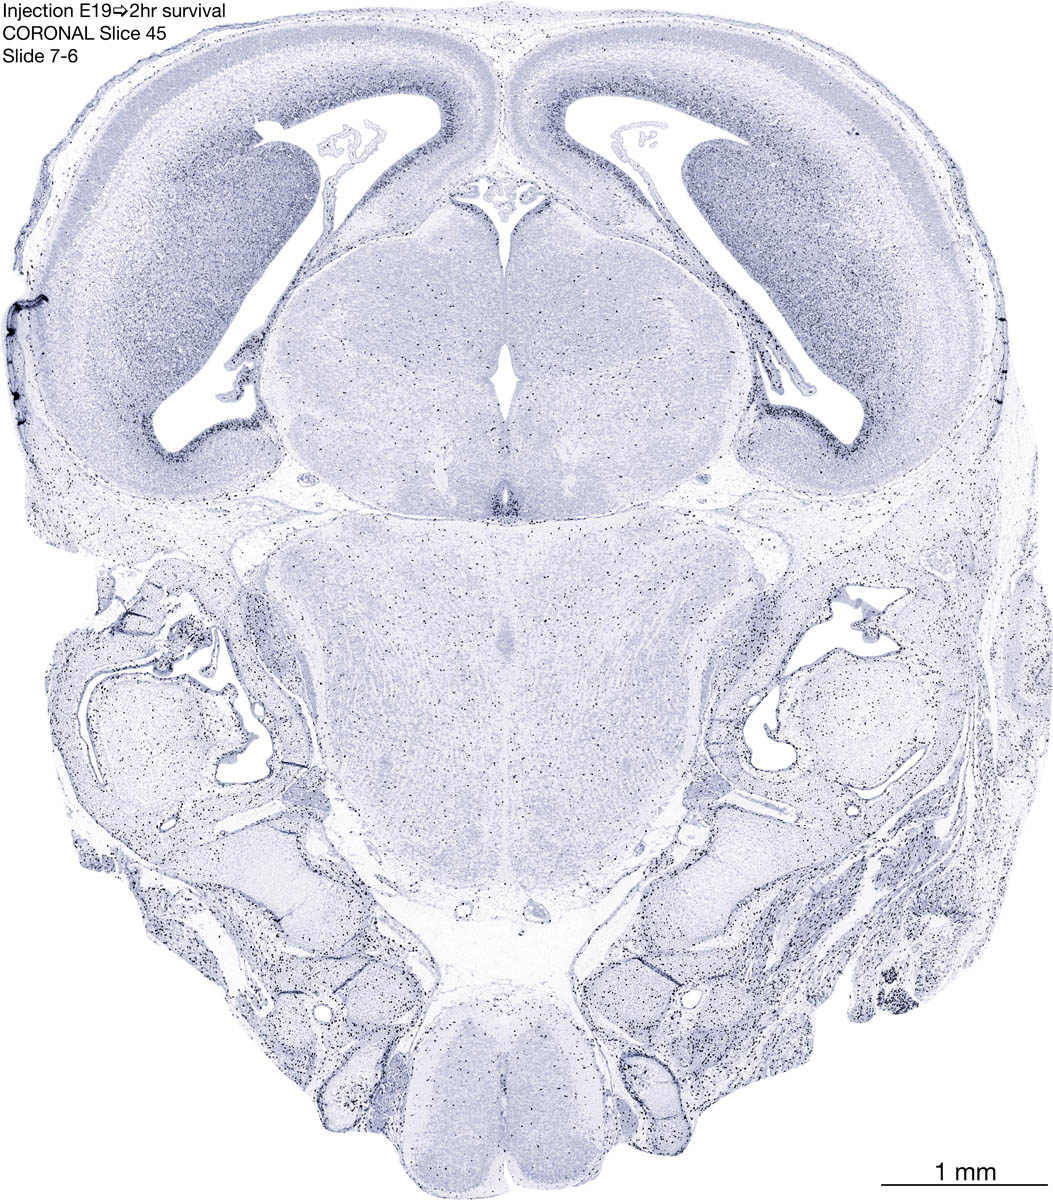

E19 2hr Survival Archived Images-Coronal The following images are from a paraffin-embedded coronally-sectioned head of an E19 rat embryo exposed to tritiated thymidine 2 hours before death. Download: Large | High Res Download: Large | High Res Download: Large | High Res Download: Large | High Res Download: Large | High Res Download: Large | High Res Download: Large | High Res Download: Large | High Res Download: Large | High Res Download: Large | High Res Download: Large | High Res Download: Large | High Res Download: Large | High Res Download: Large | High Res Download: Large | High Res Download: Large | High Res Download: Large | High Res Download: Large | High Res Download: Large | High Res Download: Large | High Res Download: Large | High Res Download: Large | High Res Download: Large | High Res Download: Large | High Res Download: Large | High Res Download: Large | High Res Download: Large | High Res Download: Large | High Res Download: Large | High Res Download: Large | High Res Download: Large | High Res Download: Large | High Res Download: Large | High Res Download: Large | High Res Download: Large | High Res Download: Large | High Res Download: Large | High Res Download: Large | High Res Download: Large | High Res Download: Large | High Res Download: Large | High Res Download: Large | High Res Download: Large | High Res Download: Large | High Res Download: Large | High Res Download: Large | High Res Download: Large | High Res Download: Large | High Res Download: Large | High Res Download: Large | High Res Download: Large | High Res Download: Large | High Res Download: Large | High Res Download: Large | High Res Download: Large | High Res Download: Large | High Res Download: Large | High Res Download: Large | High Res Download: Large | High Res Download: Large | High Res Download: Large | High Res Download: Large | High Res Download: Large | High Res Download: Large | High Res Download: Large | High Res Download: Large | High Res Download: Large | High Res Download: Large | High Res Download: Large | High Res Download: Large | High Res Download: Large | High Res Download: Large | High Res Download: Large | High Res Download: Large | High Res Download: Large | High Res Download: Large | High Res Download: Large | High Res Download: Large | High Res Download: Large | High Res Download: Large | High Res Download: Large | High Res Download: Large | High Res Download: Large | High Res Download: Large | High Res Download: Large | High Res Download: Large | High Res Download: Large | High Res Download: Large | High Res Download: Large | High Res Download: Large | High Res